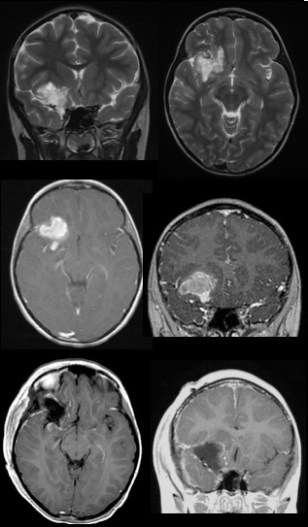

gangliogliome ; en haut : lésion épileptogène, décision de surveillance ; au centre : saignement tumoral, décision de résection ; en bas : après exérèse l’épilepsie, avec une sémiologie variable : soit crises généralisées, soit crises focales qui ont une valeur de localisation de la tumeur ; il est important de distinguer :